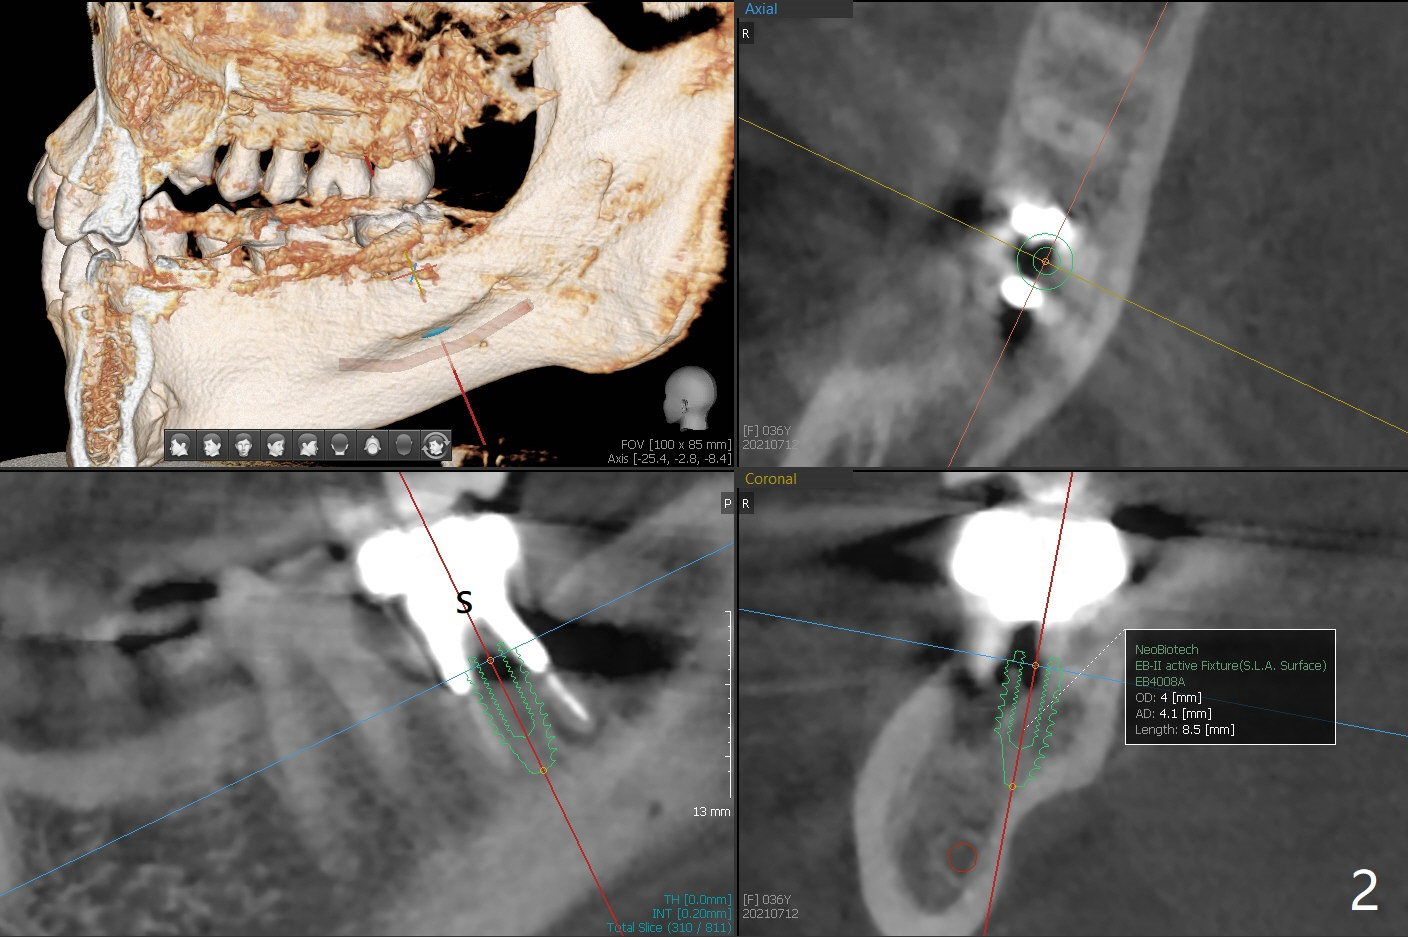

More Bone When Implant Placed in Mesial Socket

A 36-year-old woman has had an abscess and bone loss associated with the tooth #31 (Fig.1). It appears that there is less bone to support an implant when it is placed in the septum (Fig.2 S) than in the mesial socket (Fig.3 M).